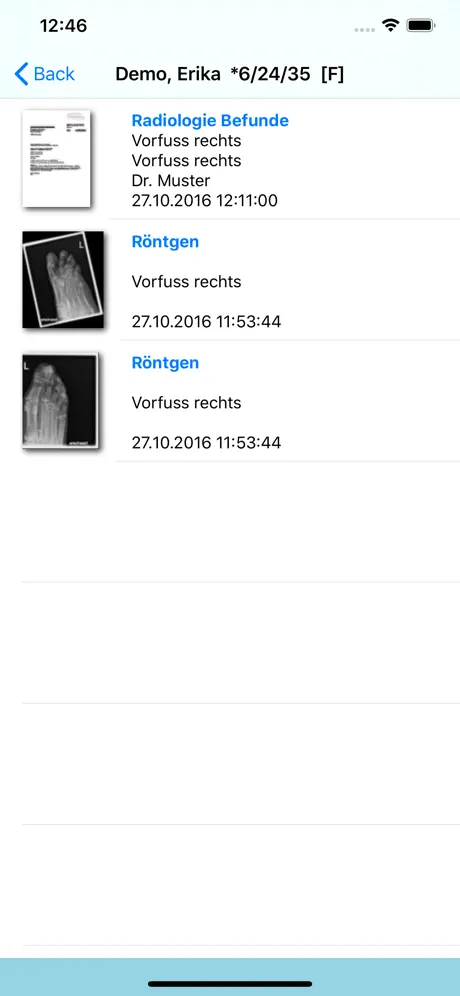

Die RVC Mobile App ist eine native iOS Applikation welche sicher

mit dem einheitlichen RVC Server kommuniziert. Mit dieser App werden iPAD, iPod touch und iPhone zu mobilen Clients die Inhalte aus RVC Clinical PACS / mDMAS intuitiv anzeigen. Dadurch ist ein ortsunabhängiger Zugriff auf das multimediale Archiv möglich. Als Mehrwert dieser Clients wurde auch eine Foto- und Videodokumentation mit integriert, sodass Fotos oder auch Videos direkt vom mobilen Endgerät in das Archiv gespeichert werden können.

- Thumbnailvorschau

- Filterfunktionen auf Dokumentenarten

- Anzeige von Dokumenten

- Thumbnailvorschau

- Filterfunktionen auf Dokumentenarten

- Anzeige von Dokumenten

Screenshots